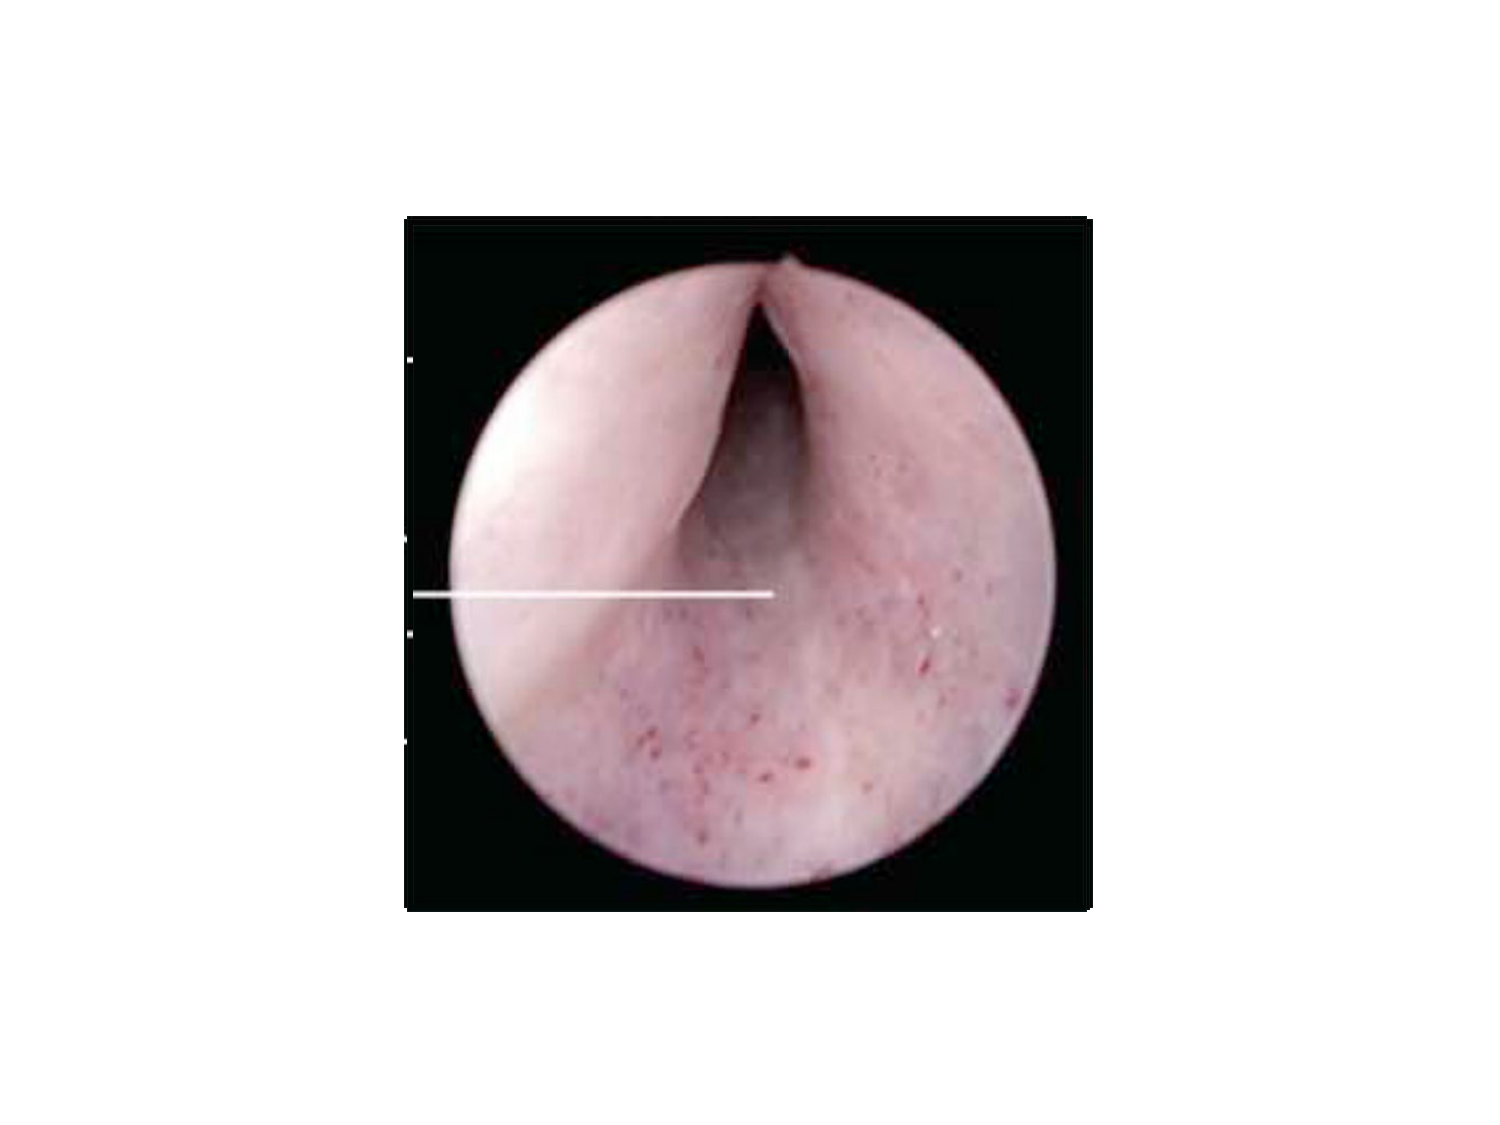

11.47 · Rein, voies urinaires et retropéritoine

Rein, voies urinaires et retropéritoine